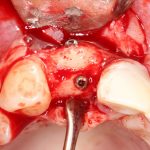

Установка имплантатов.

Напомню, что для этой работы я выбрал субкрестальные имплантаты Ankylos C/X. Они прекрасно сочетаются с любым методом остеопластики.

Я не планирую установку супраструктур или коронок, поэтому на уровень первичной стабильности можно положить болт. Даже наоборот — чем меньше крутящий момент при установке, тем лучше. Для имплантатов Ankylos и подобных им, это особенно важно. В общем, момент силы при установке — не более 10-15 Нсм.

Глянем на то, что получилось: